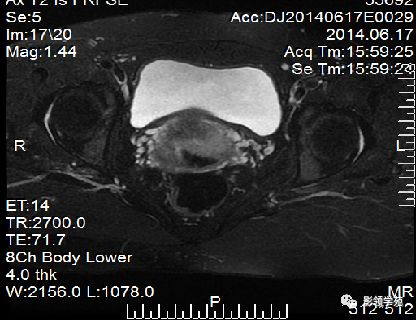

宫颈癌MRI表现

宫颈癌可表现为类圆形或不规则形肿块,在T2WI上表现为均匀或欠均匀的高信号,与正常宫颈基质及宫旁脂肪形成良好的自然对比。

- Ⅰ期肿瘤:侵犯宫颈基质,T2WI等信号肿块,宫颈管扩大及宫颈纤维基质中断